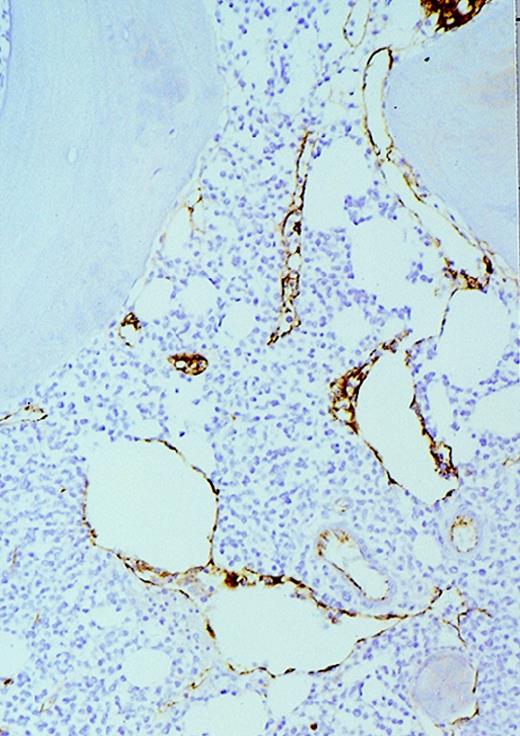

To determine whether AML cells are a source of angiogenic factors and therefore could stimulate angiogenesis in vivo, we used RT-PCR to study the mRNA expression of VEGF and bFGF in 2 human AML cell lines (HL-60 and U937) as well as in AML cells freshly isolated from untreated patients. VEGF was expressed by HL-60 and U937 cells as well as all fresh AML samples (Figure 5A). The extent of VEGF mRNA expression varied among the different patient isolates tested (Figure 5A). In contrast, only HL-60 cells and 3 of 4 fresh AML cells expressed bFGF (Figure 5B). Immunohistochemical stains of cytospins from HL-60, U937, and fresh AML samples showed that they expressed VEGF protein (Figure 6).

Expression of VEGF protein in AML cells.

Cytospin of AML cells freshly isolated from an untreated patient was stained immunohistochemically for VEGF expression (see Methods). AML cells expressed VEGF protein in the cytoplasm, which is typical of this growth factor. Similar results were obtained with HL-60, U937, and 5 other fresh AML samples.